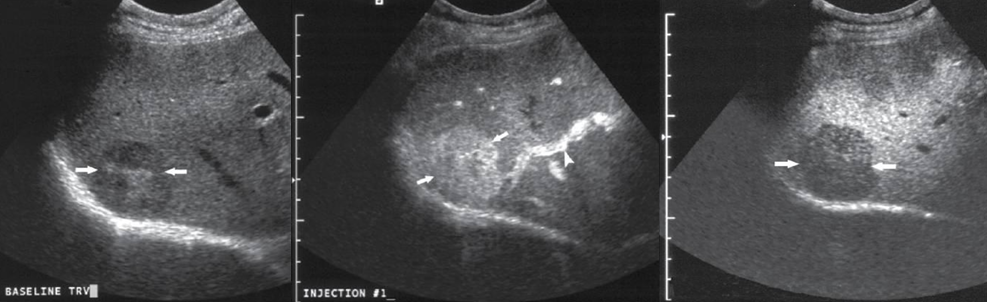

what lesion is seen on this CEU?

HCC